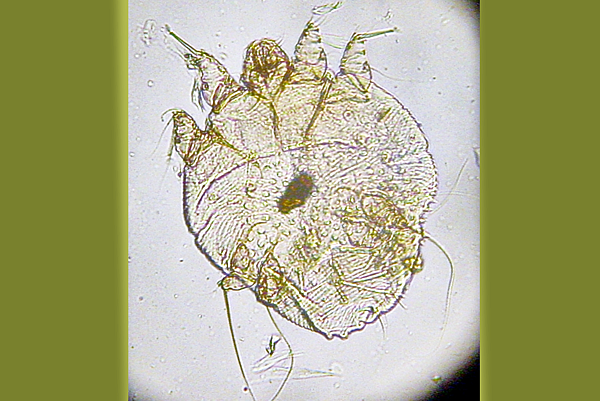

疥蟎.png

疥蟎是一種肉眼幾乎看不見微小寄生蟎,會鑽入皮膚,並引發疥瘡。